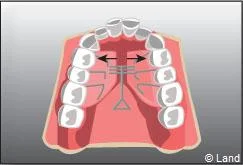

De plus, il est opportun de corriger très tôt certaines malpositions. Les appareils généralement utilisés sont amovibles avec une armature en résine, mais peuvent aussi être fixes à l’aide de bagues sur les premières molaires définitives.. Suivant leurs conceptions et la manière dont ils sont portés, ils auront une action sur la position des dents mais aussi sur la croissance.